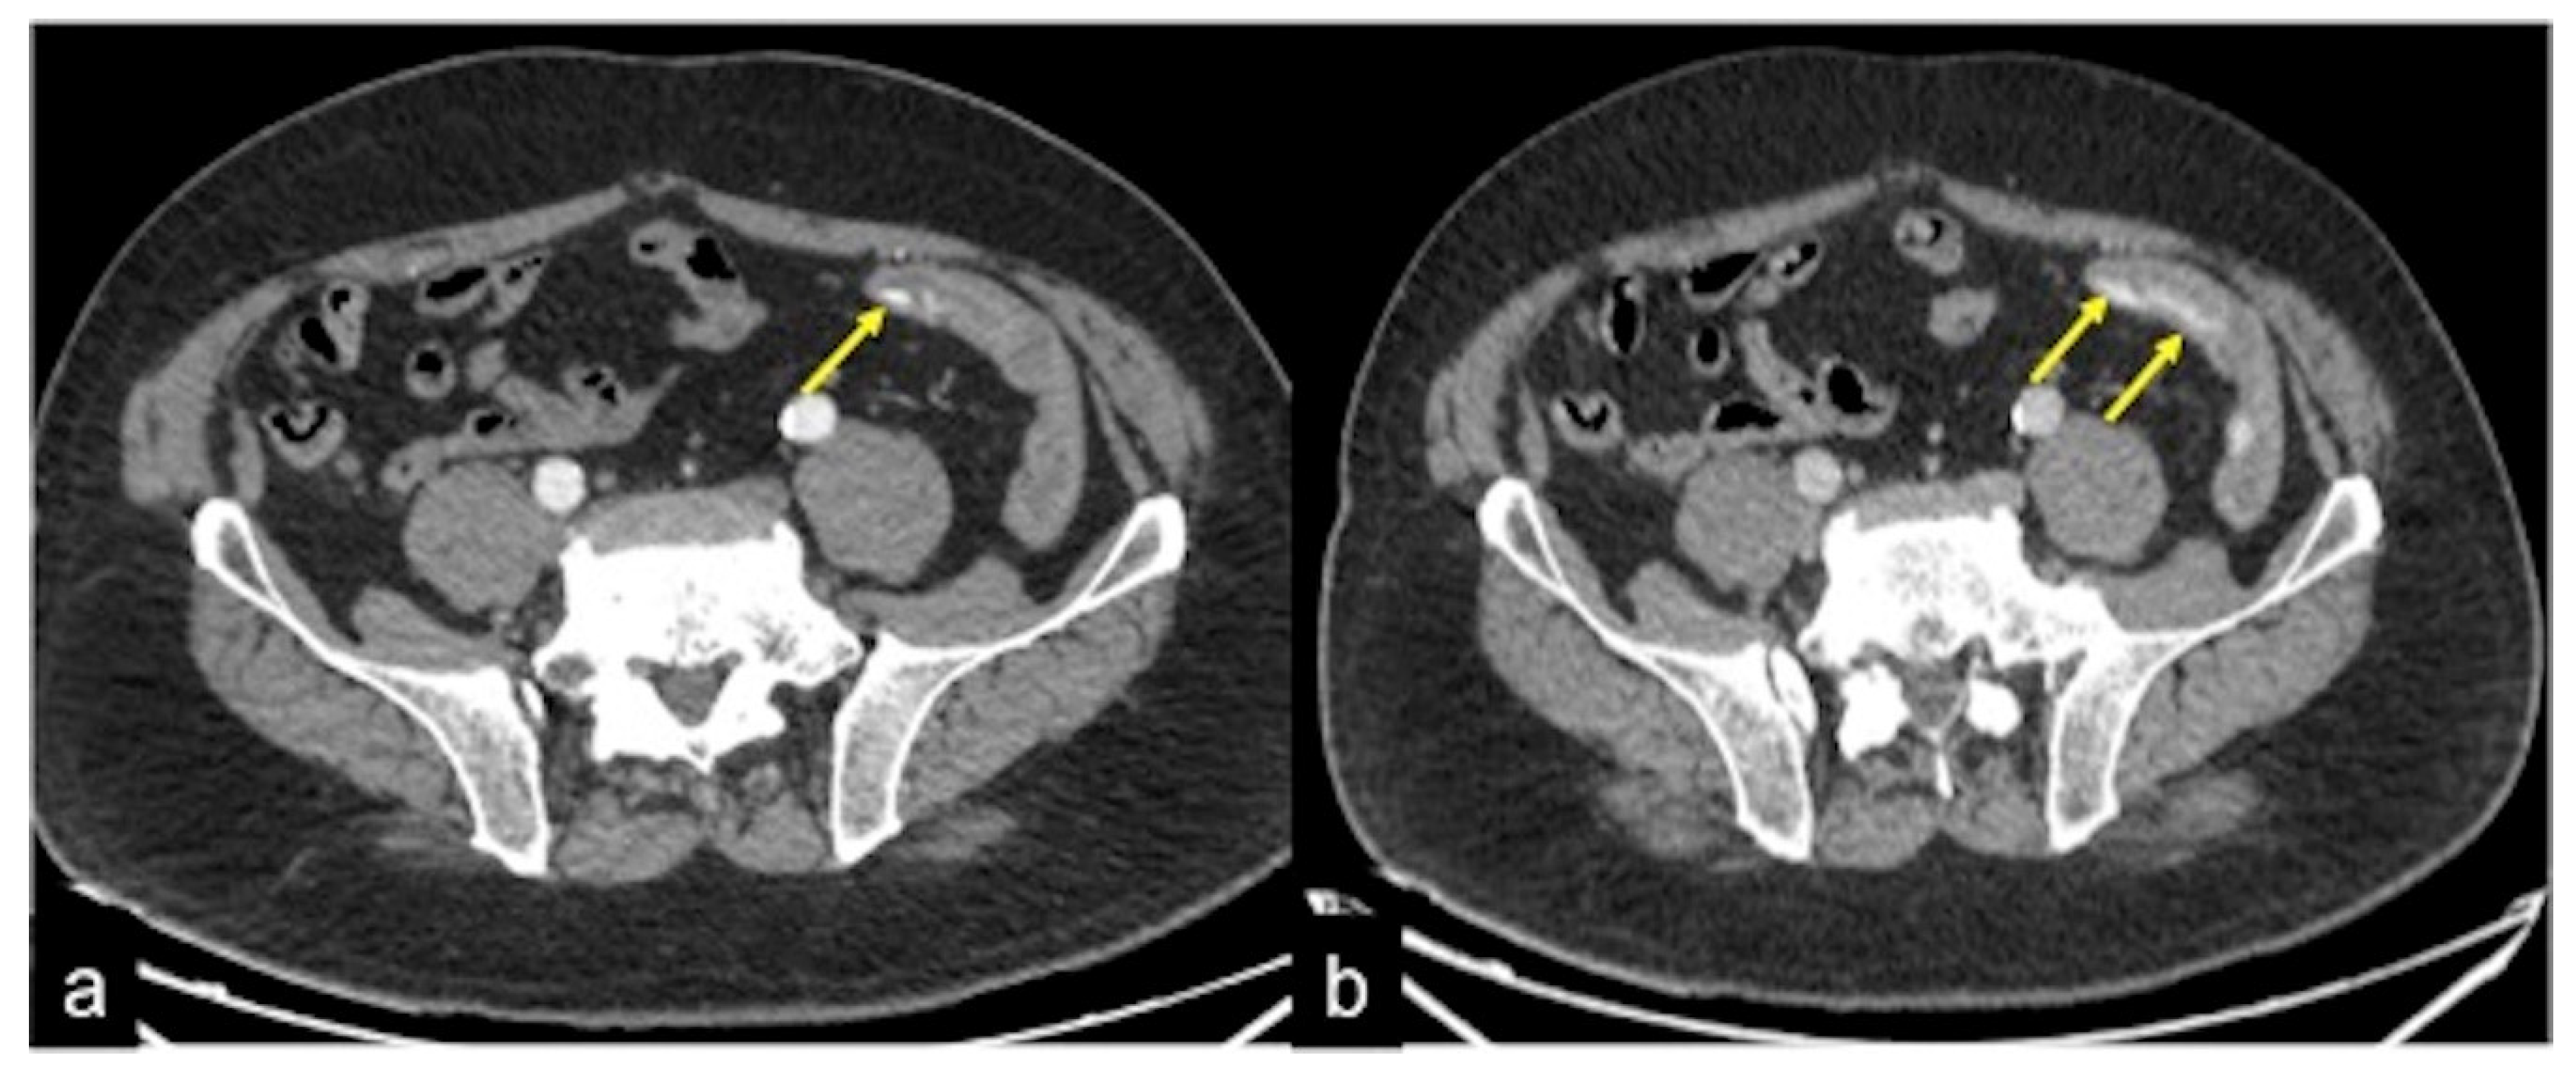

| Angiodysplasia (Figure 11) | Obscure bleeding. | Abnormally dilated, tortuous, thin-walled vessels involving small capillaries, veins and arteries. |

| Angiodysplasia (Figure 5 and Figure 34) | Asymptomatic or bleeding. | Small hyperdense nodules within the intestinal wall, best defined in the portal phase of the study. |